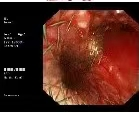

患者朱某某,一年前因咳嗽、咯血确诊为右肺鳞癌,曾接受化疗及免疫治疗,后因免疫相关不良反应调整治疗方案。近期因咳嗽加重、活动后气促显著入院,呼吸困难明显,日常活动严重受限。气管镜检查证实气管及右主支气管被新生物广泛阻塞,狭窄程度超90%,气道通气功能濒临衰竭。

气管镜下可见右主支气管新生物